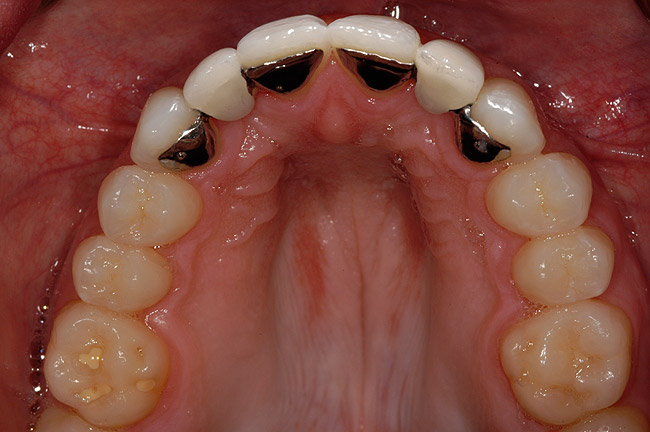

Figure 6 The orthodontic treatment created divergence of the coronal tooth structure and convergence of the roots around the edentulous spaces.

Figure 6